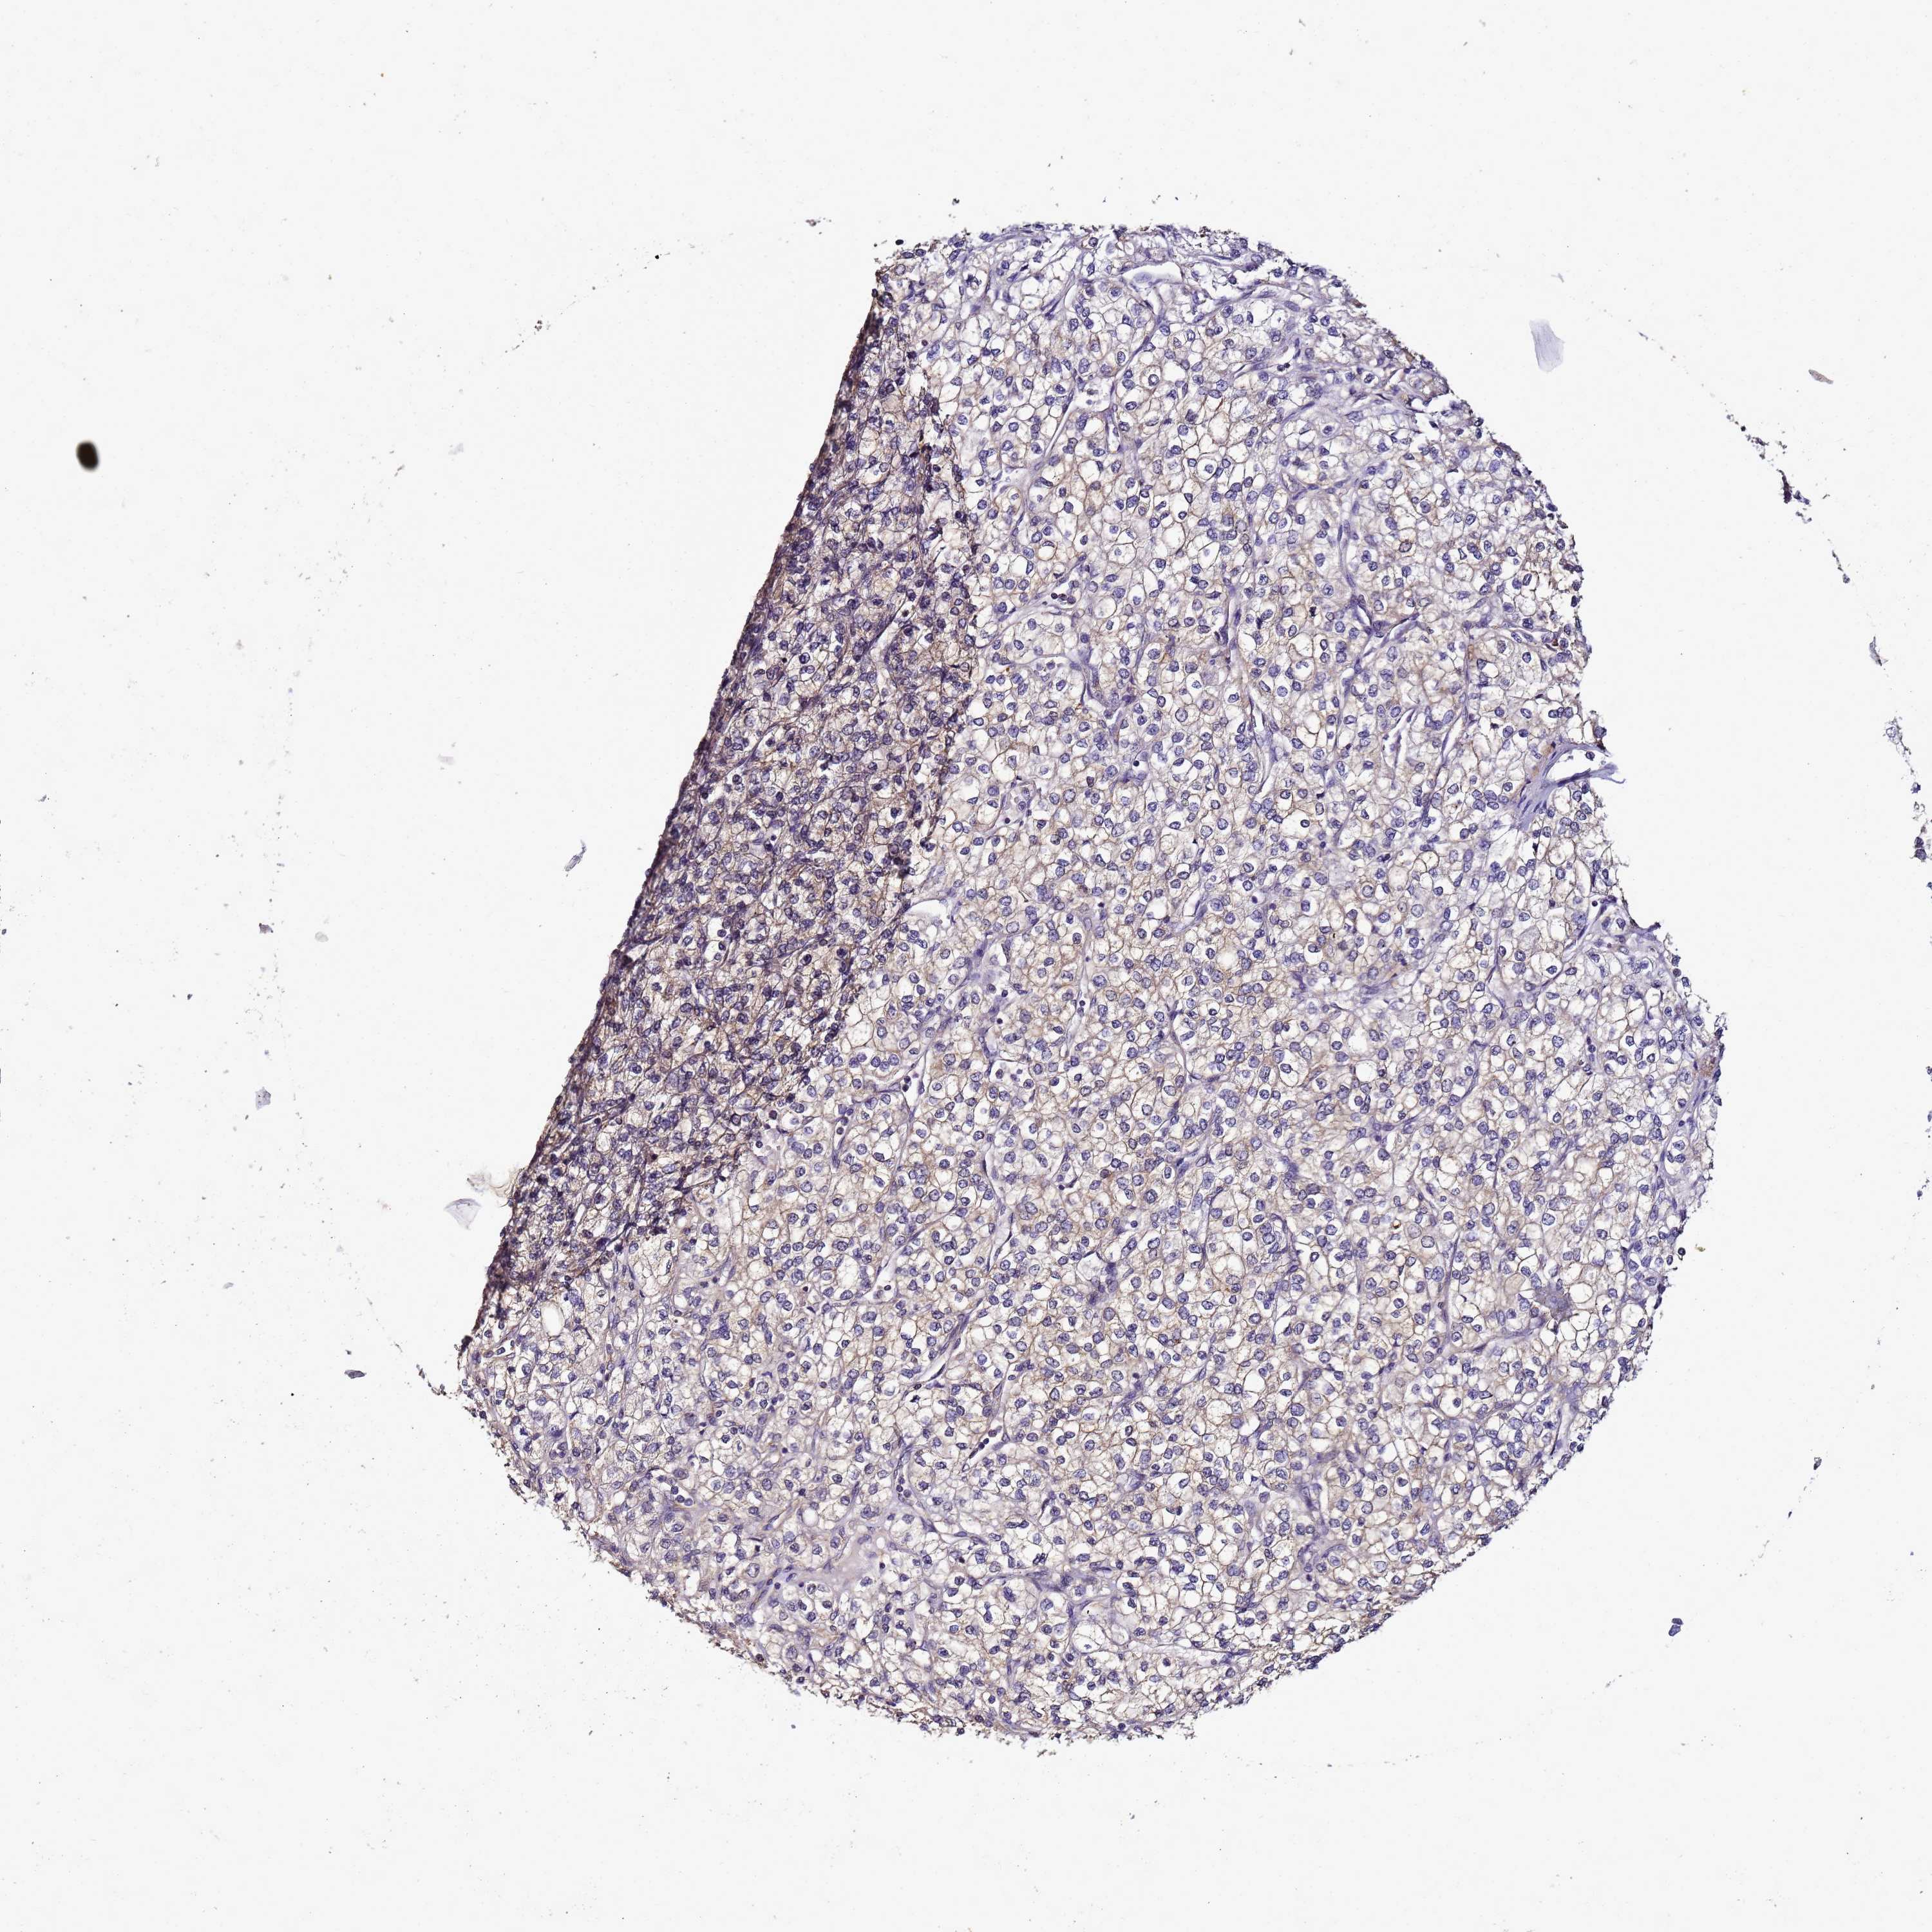

CANCER RENAL CANCER Show tissue menu

KICH TCGA KIRC TCGA KIRC VALIDATION KIRP TCGA PROTEIN RCC CPTAC PROTEIN EXPRESSION

ENOPH1 is potential prognostic, high expression is unfavorable in Kidney Chromophobe (TCGA)

Average pTPM 50.2

Number of samples 64